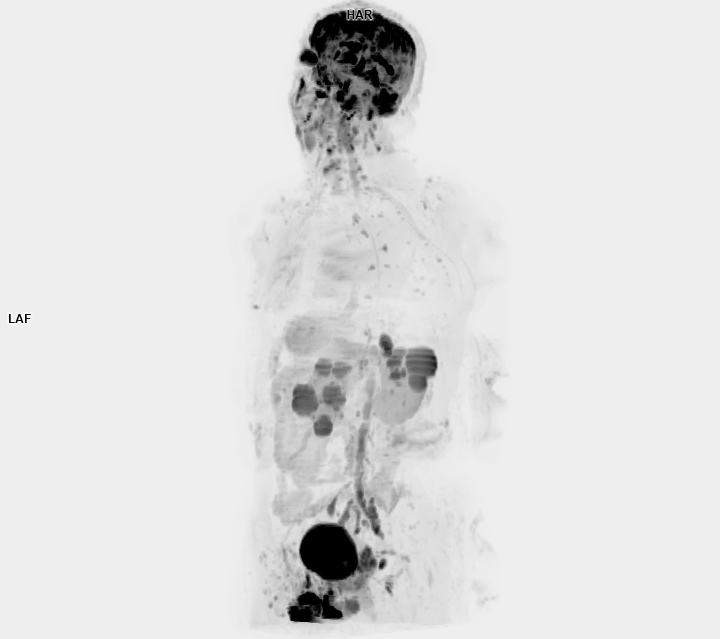

3 Tesla MR Çekim Görüntüleri

• 3 Tesla MR Çekim Görüntüleri